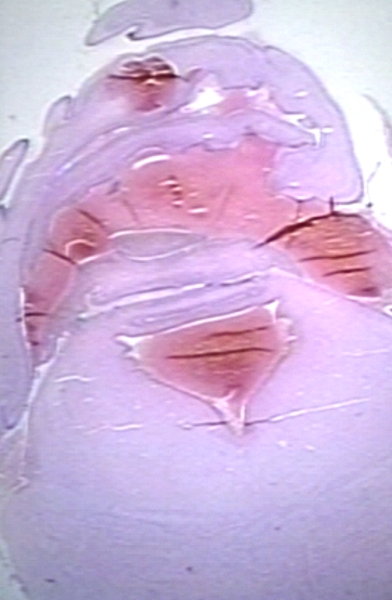

HISTOLOGY: NERVOUS: BRAIN: HEMORRHAGE, GERMINAL MATRIX INTO VENTRICULAR SYSTEM AND SUBARACHNOID SPACE; FETAL BRAIN